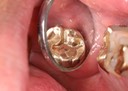

Joe Cha #18 prep

Joe Cha #18 pre-cementation